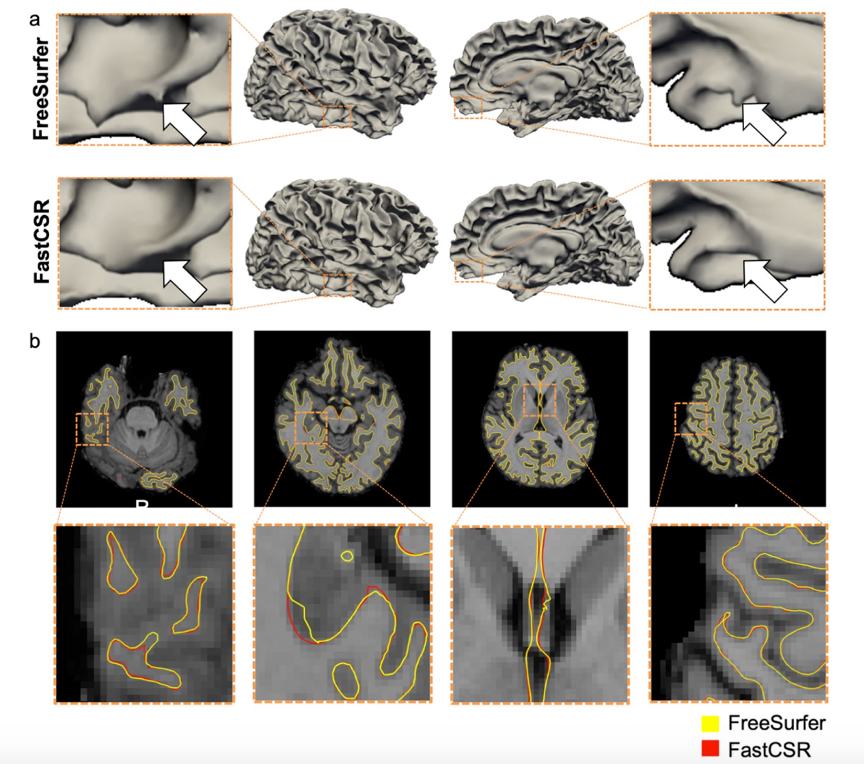

研究人员比较了FastCSR与FreeSurfer皮层重建结果的几何结构,两种算法的几何结构高度一致,皮层边界高度重合。

研究人员进一步测试了针对较差影像质量或有脑损伤被试影像数据重建效果,结果显示在对一些影像质量较差的数据进行皮层重建后,FreeSurfer在中央前回和中央后回边缘出现锯齿状,而FastCSR重建出的图像则更加平滑;表明FastCSR可适用于低质量影像数据的皮层重建。对具有脑损伤患者(如脑卒中、脑外伤、脑肿瘤)的影像数据进行重建是具有重要意义但仍是难以解决的挑战。研究人员尝试对3名脑卒中损伤患者影像进行重建,使用FastCSR能够成功进行皮层重建,且能看到脑损伤区域,而FreeSurfer无法完成重建,证明FastCSR可用于脑损伤患者的影像数据重建,对于临床上经常遇到的脑部有变形的患者进行皮层重建的问题,提供了一种可行的解决方案。